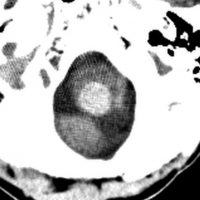

全脳照射後の脳内石灰化(幼児例)

20年以上前のことですが,髄芽腫の1歳6ヶ月の子どもに25グレイの全脳照射をしました。これは15年後のCTです。

脳の萎縮は目立ちません。認知機能は低いのですが支援を受けて学校へ行けています。下垂体機能は低下して成長ホルモンなどの補充をして普通に暮らせています。

CTで,両側の大脳基底核(被殻と淡蒼球)と視床後部に石灰化がみられます。乳幼児期に放射線治療を受けた子どもに見られるものです。